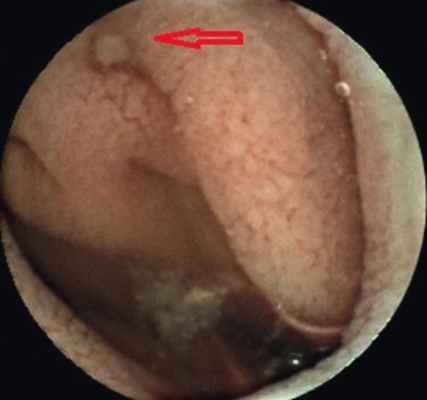

Пациентка В . , 19 лет, с подтвержденным диагнозом «болезнь Крона (язвенно-геморрагический энтерит)» с 2012 г. неоднократно находилась на обследовании и лечении в отделении воспалительных заболеваний кишечника Московского клинического научно-практического центра. Длительное время получала месалазин, азатиоприн, инфликсимаб; неэффективность проведенного лечения послужила поводом для назначения биологической терапии (адалимумаб). Однако стойкой ремиссии добиться не удавалось. При очередном обследовании в марте 2015 г. пациентке была выполнена колоноскопия, во время которой выявили незначительные воспалительные изменения ободочной кишки и терминального отдела подвздошной кишки: афтозный колит, афтозный терминальный илеит. Данные, полученные при традиционной эндоскопии, не соответствовали клиническому состоянию больной. Для оценки распространенности и степени поражения кишечника ей была назначена КЭ. В результате видеокапсульного исследования определено поражение глубоких отделов тонкой кишки на значительном протяжении в виде множественных язв и отека складок, а также обнаружено сужение просвета тонкой кишки ( рис. 1-4 ).

Рис. 1. Язва слизистой оболочки тонкой кишки. Фото авторов